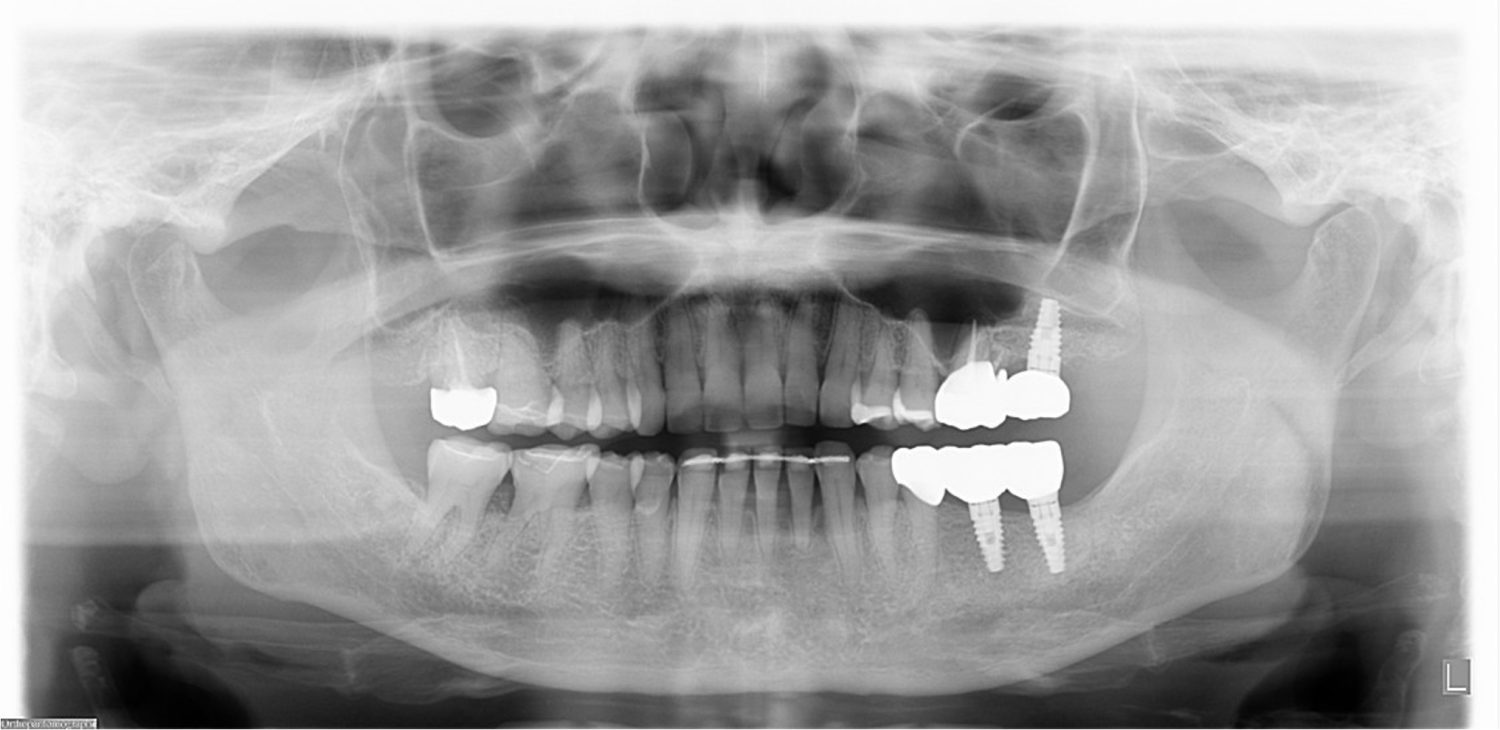

| 主訴 | 歯がグラグラで噛むことができない。インプラントをして欲しい。 |

| 治療内容 | 歯周病で骨の吸収が重度で保存不能なため抜歯、仮の入れ歯を作り、6ヶ月の抜歯窩の治療の後に、インプラントのCTによる診査診断を行い、下顎に6本インプラント埋入と同時に仮歯を入れる。その後、上顎は8本のインプラント埋入と同時に仮歯を入れる。左右上6はソケットリフトによる上顎洞拳上術を行う。その後免荷期間6ヶ月待ってセラミックを用いた上部構造作製、装着しメンテナンスに移行する。 |

| 治療費 | 9,000,000円(税込) |

| 治療期間 | 2年3ヶ月 |

| 治療回数 | 90回 |

| 想定されたリスク | 重度の歯周病により無歯顎になったため、プラークコントロール不良による、術後のインプラント周囲炎が懸念される。歯冠の部分はセラミックなため欠ける可能性がある。 |